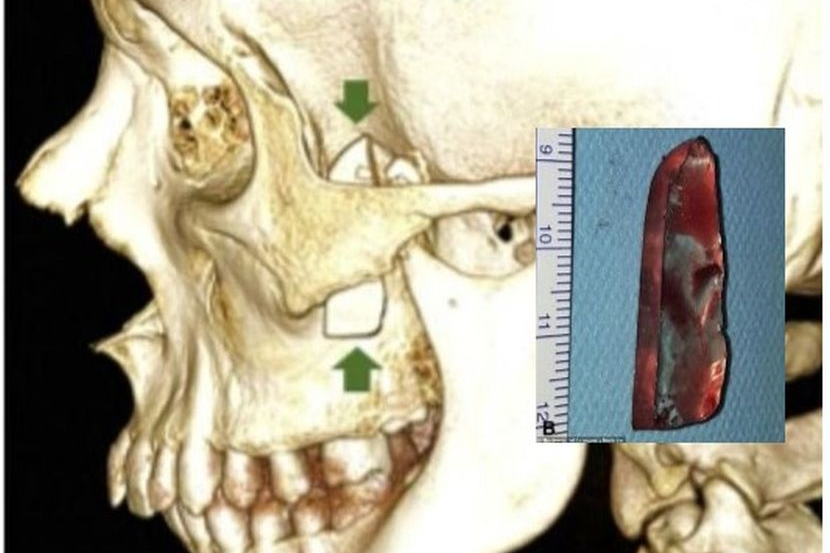

Rawatan X-ray mendapati sekeping objek tajam dikenal pasti sebagai pisau nipis tertusuk di bahagian dalam mukanya yang terselindung di bawah tulang pipi.

Doktor di Hospital Universiti Rocio, Sevilla yang merawatnya memberitahu, objek yang ditemui itu berada di tempat yang sangat jarang berlaku. -Dailymail.co.uk